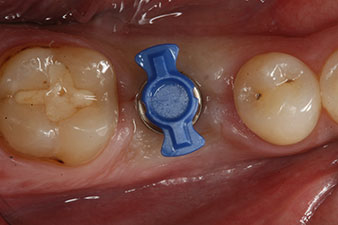

En outre, après avoir vissé une tige de mesure (SmartPeg) spécialement conçue pour l'implant, la valeur ISQ a été mesurée à l’aide de la sonde du module W&H Osstell ISQ.

Ce module est fourni en option avec l’Implantmed de W&H et est fixé au moteur d’implantologie (cf. Fig. 11). La valeur ISQ adimensionnelle mesurée immédiatement après l’insertion était de 64 dans l’axe oro-vestibulaire et de 68 dans l’axe mésio-distal (valeur maximale = 100).